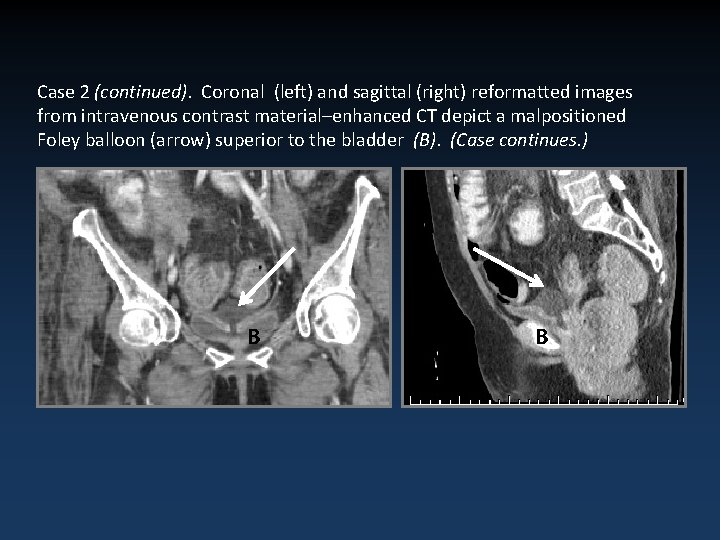

Case 2 (continued). Coronal (left) and sagittal (right) reformatted images from intravenous contrast material–enhanced CT depict a malpositioned Foley balloon (arrow) superior to the bladder (B). (Case continues. ) B B